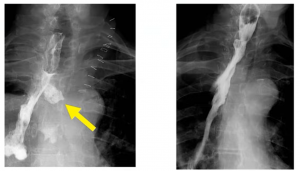

Below you can see a cervical anastomotic leak Type 1:

A radiological intra-thoracic Type 1 leak: